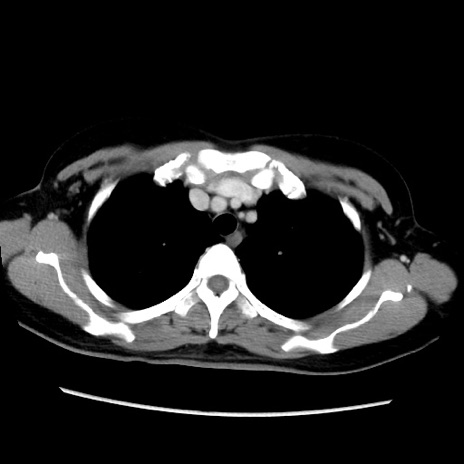

MRI(4日後)

【症例】40歳代女性

【主訴】上下腹部痛

【現病歴】2日目から下腹部痛あり。夜間は痛みで眠れなかった。昨日より上腹部痛と下痢が出現。臥位で痛みは軽快したため、休んでいた。本日になって臥位でも立位でも痛みが強くなってきたため救急要請。

【既往歴】子宮内膜症

【身体所見】部:平坦・軟、左上下腹部に圧痛あり、反跳痛あり。

【データ】WBC 21800、CRP 26.78